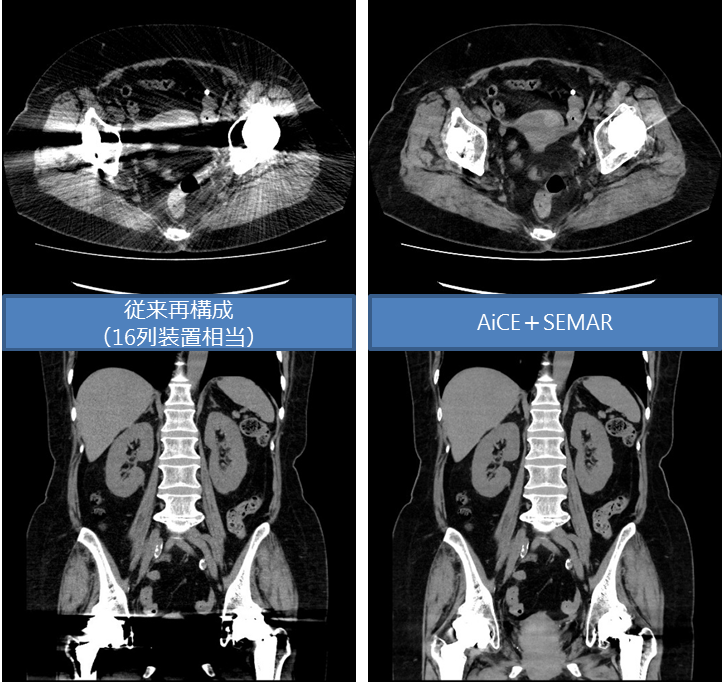

当院では、2020年5月に最新型CTである80列CT Canon Aquilion Lightning / Helios i Edition (以下、Helios i Edition)を導入しました。Helios i Editionは、Ai技術を用いた画像再構成技術であるAiCE-i を搭載した最新機種です。AiCEを用いることで、CT装置がもっている空間分解能を最大限に引き出しながら、高いノイズ低減効果を得ることができます。この技術によって大幅な被ばく低減と画質向上を実現しました。

さらに、新しく体内金属からの画像劣化を最小限に抑える技術(SEMAR)も搭載しており、股関節など金属置換後の患者様にも高画質の検査が可能となりました。

<股関節金属置換後>